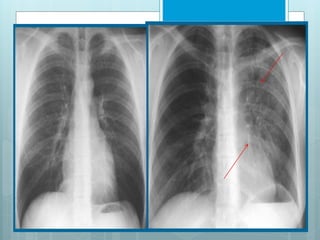

LUL Collapse

 Left major fissure is displaced

ant, roughly parallel to ant

chest wall.

 On PA view it produces a

faint, hazy opacity in left upper

hemithorax, that can be

mistaken for pleural

thickening.

 Left cardiac contour is frequently obscured by lingula.

 Hyper-expanded left lower lobe occupies most of left

hemithorax, with its superior segment occupying apex,

mimicking an aerated upper lobe.

 Left hilar structures are retracted cephalad.